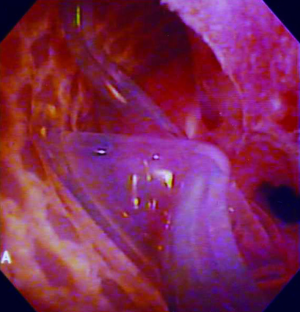

ISU is performed at the time of AUS device explantation. Figure 1 shows an endoscopic view of the eroded AUS cuff. After the cuff is removed, Foley catheter is inserted to facilitate reconstruction, and when necessary, urethroscopy with wire placement ensures accurate placement of a 14-French Council tip catheter (Figure 2). ISU is accomplished by reapproximating the urethral defect with full-thickness, interrupted 2-0 absorbable monofilament suture over the catheter (Figures 3 and 4). This abbreviated approach is performed without further mobilization of inflamed tissues within the already hostile operative field. The urethral Foley catheter is left in place for three weeks with voiding cystourethrogram (VCUG) imaging done at the time of removal.